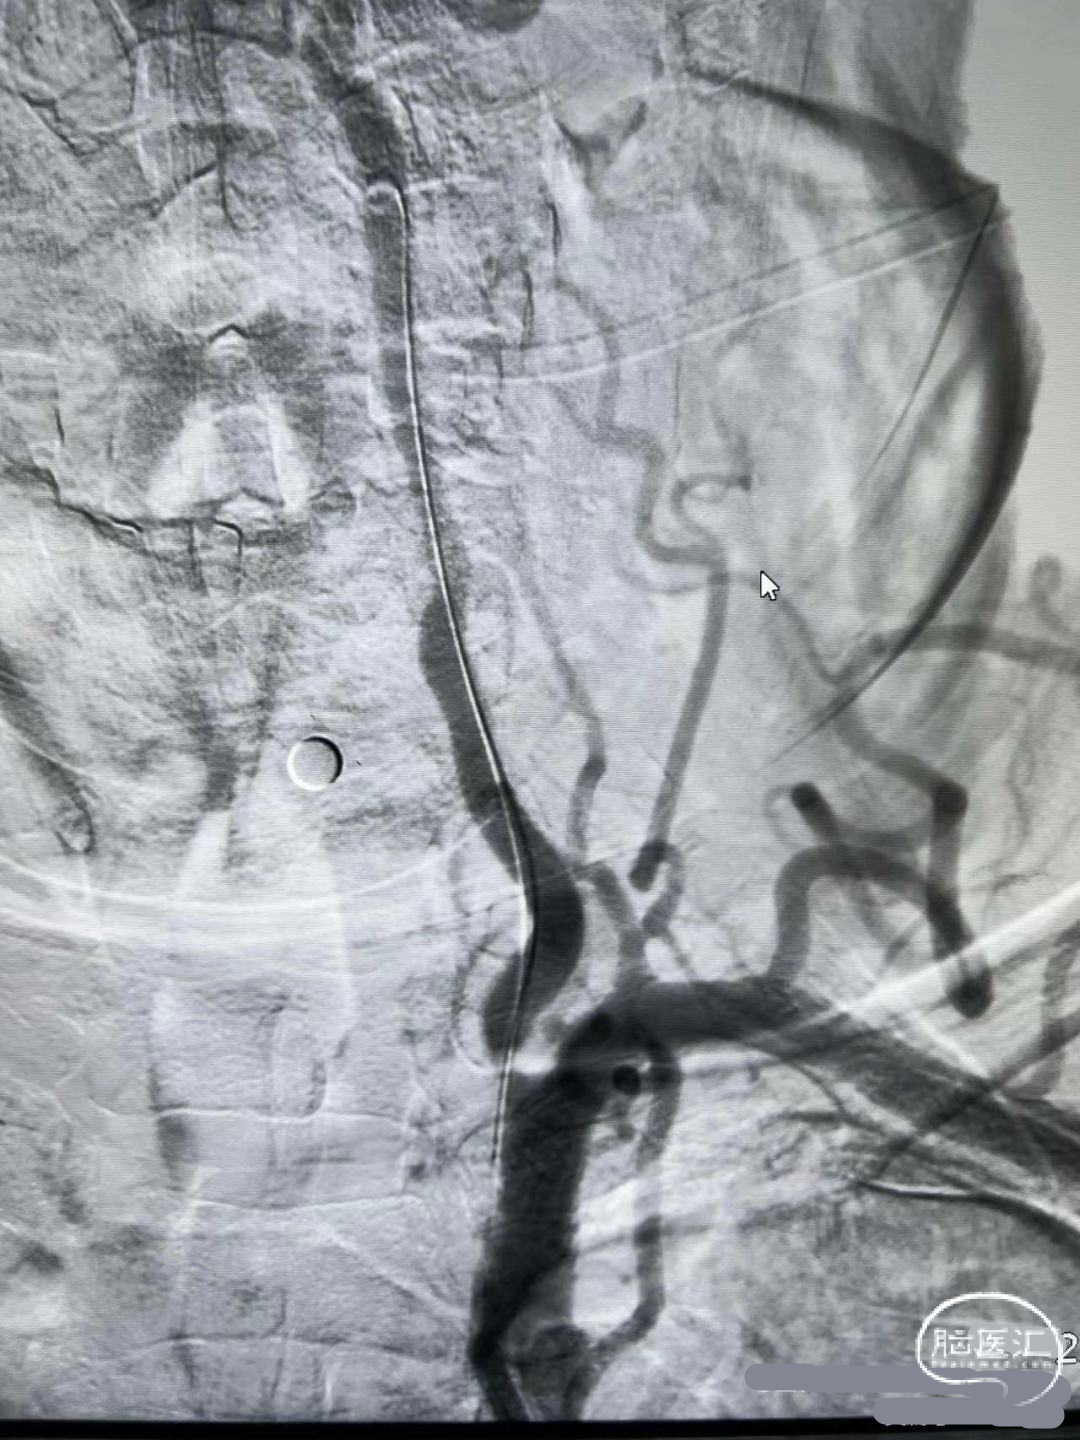

术前DSA影像

右侧颈内动脉起始部中度狭窄,未见血流向后循环代偿。

左侧颈内动脉造影提示后交通开放,代偿供应后循环。

左侧椎动脉开口重度狭窄,前向血流缓慢,V4闭塞。